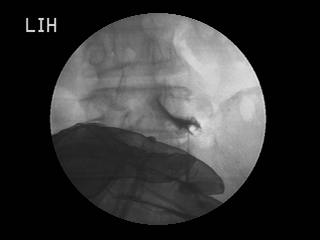

– 오십견으로 어깨 관절이 심하게 굳어 있을 때 (수압팽창술) 어깨 통증이 심하고 팔이 안 올라가는 경우 어깨 관절이 염증으로 좁아져 있는 상태입니다. 이 때 C-arm 기계를 이용하여 좁아진 어깨 관절낭 부위를 직접 확인하고 관절강을 넓히고 염증을 줄이는 치료를 할 수 있습니다. 그 밖에도 고관절, 천장관절통 등 여러부위에서 C-arm 기계를 이용한 치료가 가능합니다.